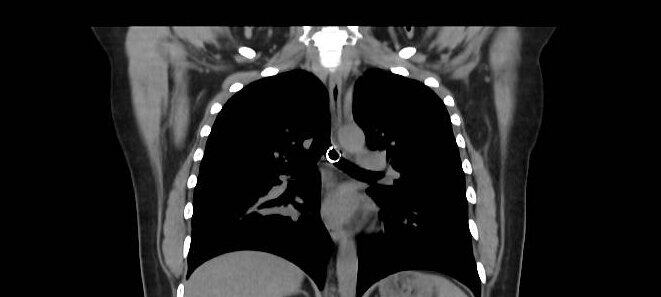

Mesec dana sam uporno kašljala: Lekari nisu mogli da veruju šta su mi pronašli u plućima, 0,5 milimetara od aorte

1 / 4

Jam Press / Jam Press / Profimedia